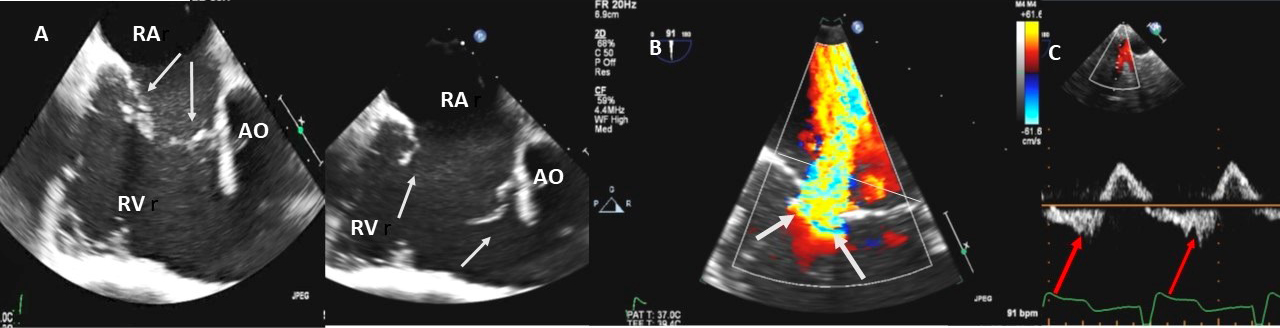

In adults TR is most commonly secondary (or functional), with normal leaflets and chords. Dilatation of the right atrium and RV with dilation of the tricuspid annulus is the most cause of secondary TR [32] (Fig. 4A–C). In an echocardiographic review of patients without primary tricuspid valve disease [33], severe TR was associated with higher pulmonary artery systolic pressure (PASP), atrial fibrillation, right atrial and RV enlargement, LV dysfunction, and primary mitral valve disease. In patients with concomitant mitral valve disease, TR is referred to as functional and is considered to be caused by filling pressure elevation in left heart, resulting in eventually tricuspid annular dilation and the tethering of tricuspid leaflets induced by RV enlargement [34, 35, 36]. This may also be true in patients with late TR after left side valve surgery [37]. Secondary TR in patients with right ventricular pressure and/or volume overload is caused by annular dilatation and increased tricuspid leaflet tethering [2].

Fig. 4.Functional Tricuspid regurgitation. (A) TEE mid esophageal inflow-outflow view shows a dilated RV and tricuspid annulus (white arrows). (B) TEE 4 chamber view color Doppler showing centrally directed severe tricuspid regurgitation with PISA (white arrows). (C) PW Doppler showing systolic hepatic flow reversal, which suggests severe TR (red arrows). RA; right atrium; RV, right ventricle; AO, aorta.